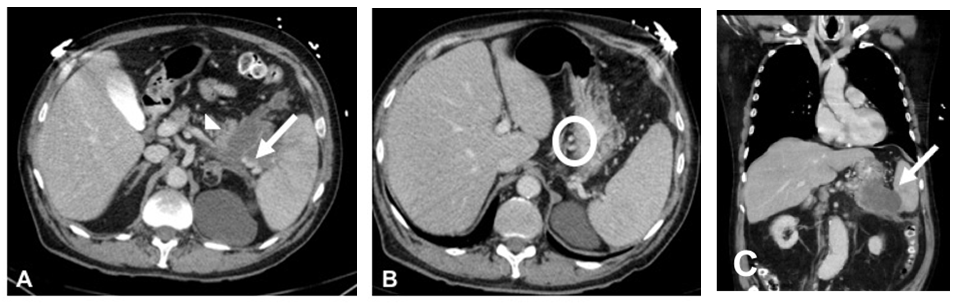

A 71-year old man presented to the emergency department with acute onset massive hematemesis and epigastric pain. He denied jaundice, NSAID use or prior hematemesis. Relevant medical history included heavy tobacco use in the past but denied alcohol use. He presented hypotensive with tachycardia. He had tenderness in the epigastric and left upper quadrant without peritoneal signs. Hemoglobin was decreased at 8.3g/d from baseline 12. Total bilirubin and liver function tests were within normal limits. Contrast enhanced CT of the abdomen and pelvis done in the ER showed splenic vein thrombosis (Figure 1A, arrowhead), gastric varices (Figure 1B, circled) with active hemorrhage noted, and a 5cm mass in the pancreatic tail extending into the splenic hilum (Figure 1C, arrow). No changes of cirrhosis were noted in the liver, but possible peritoneal implants were noted. Given the active gastric variceal hemorrhage and the patient’s instability, emergent endoscopy was deferred. The patient was stabilized in the ICU. Given the suspected metastatic nature of his pancreatic cancer, the patient underwent successful splenic artery embolization using 700micron embozene particles (Figure 2) and the patient did not experience any further episodes of hematemesis. After he was stabilized tissue diagnosis of metastatic pancreatic adenocarcinoma was confirmed with peritoneal biopsy. Other labs were notable for an elevated CEA at 45.5ng/mL and CA 19-9 of >10,000U/mL.

Figure 2 Splenic artery angiogram. (A) Pre-embolization. (B) Post-embolization with near complete stasis of flow in splenic artery and minimal residual parenchymal enhancement.